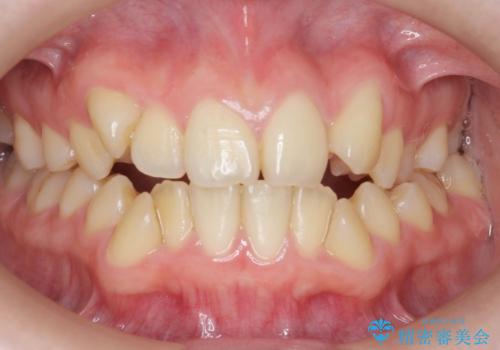

[前歯のねじれ 部分]ワイヤーとマウスピースの併用矯正治療

担当医 大元洋佑